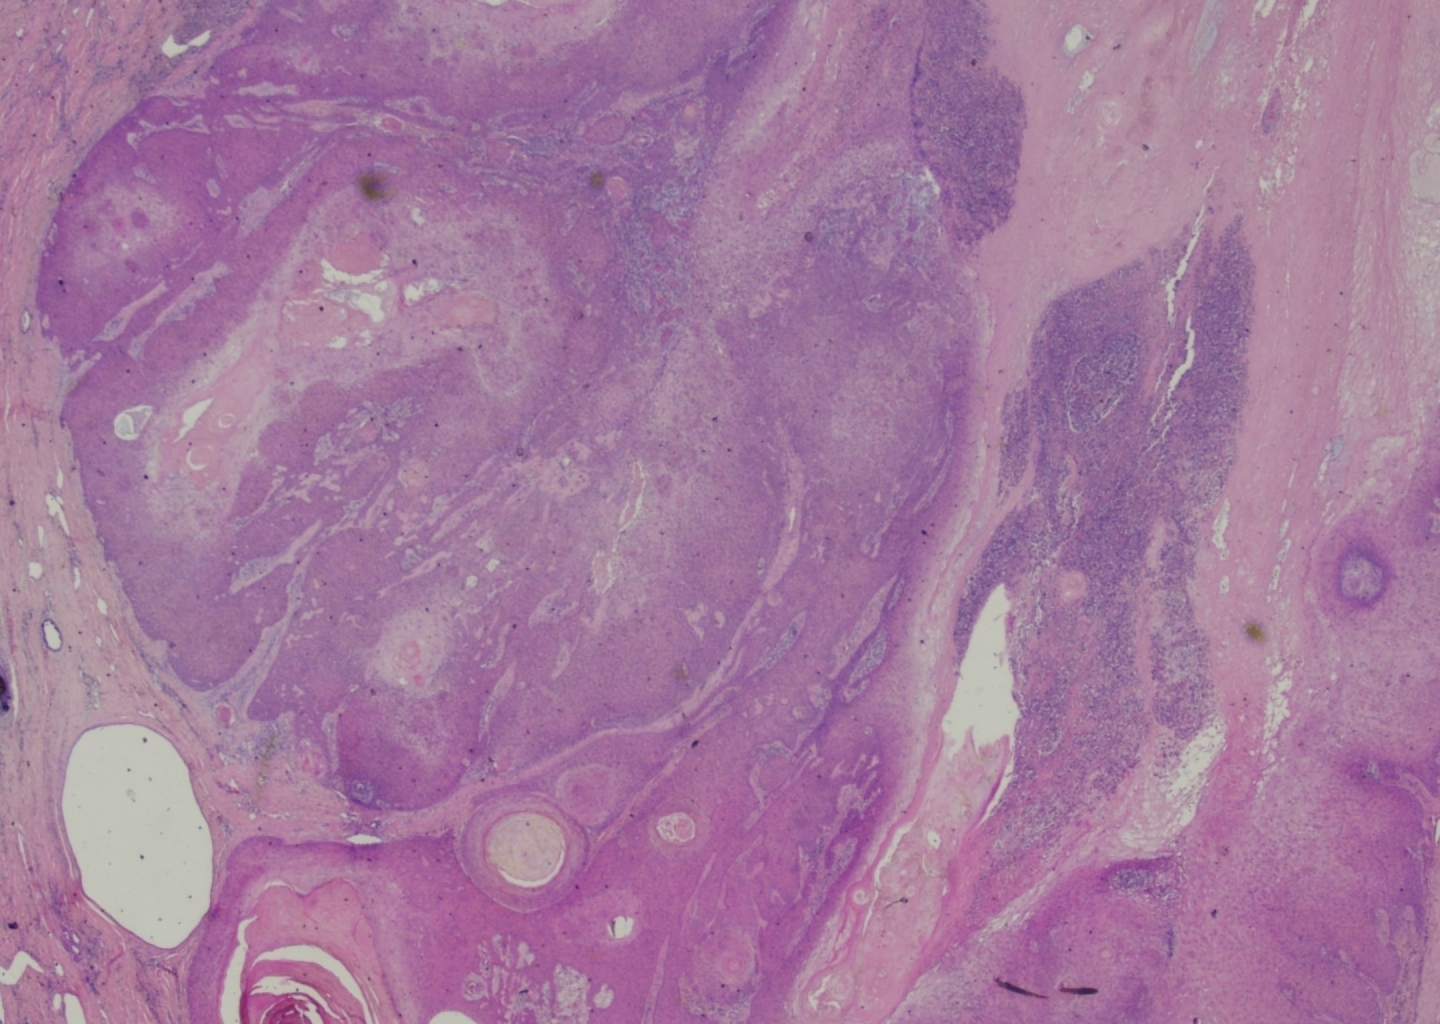

Complete excision of the horn was done with V-Y plasty, and the tissue was sent for pathological examination. A coiled horn measuring 26 cm with an attached skin ellipse measuring 4.5 x 3 cm was received in the pathology laboratory. Histopathological examination revealed a well-differentiated squamous cell carcinoma with keratin horn formation (Figs. 3 and 4). The tumour involves the upper dermis only with no vascular or perineural invasion. The lesion was completely excised with clear excision and deep margins measuring > 4mm. The patient’s surgical excision site healed well (Fig. 5), and there were no clinical recurrences over the 5-year period (the patient was seen at 3, 4, and 5 years after excision).